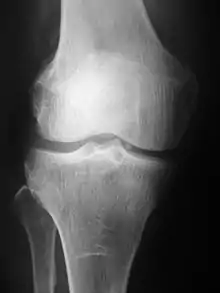

Projection (plain) radiography

Radiographs (originally called roentgenographs, named after the discoverer of X-rays, Wilhelm Conrad Röntgen) are produced by transmitting X-rays through a patient. The X-rays are projected through the body onto a detector; an image is formed based on which rays pass through (and are detected) versus those that are absorbed or scattered in the patient (and thus are not detected). Röntgen discovered X-rays on November 8, 1895, and received the first Nobel Prize in Physics for his discovery in 1901.

Plain radiography was the only imaging modality available during the first 50 years of radiology. Due to its availability, speed, and lower costs compared to other modalities, radiography is often the first-line test of choice in radiologic diagnosis. Also despite the large amount of data in CT scans, MR scans and other digital-based imaging, there are many disease entities in which the classic diagnosis is obtained by plain radiographs. Examples include various types of arthritis and pneumonia, bone tumors (especially benign bone tumors), fractures, congenital skeletal anomalies, and certain kidney stones.